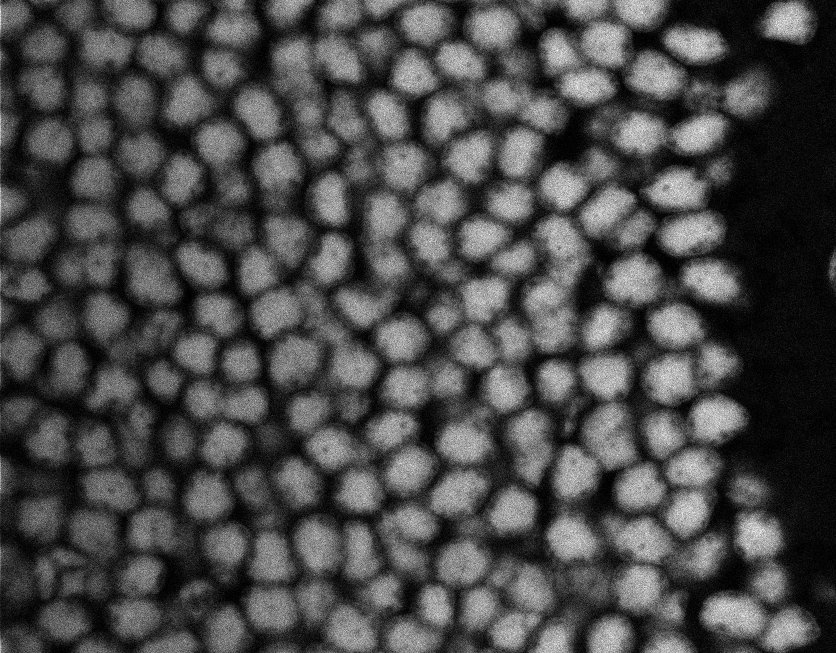

Nuclei

Nuclei - Bis

Nuclei - Bip